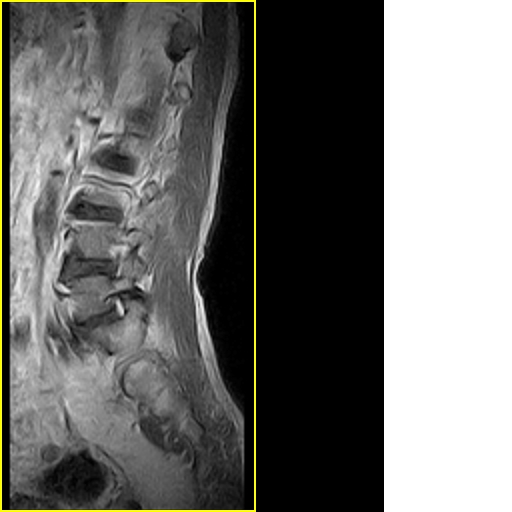

标题: MRI0859:[原创]腰椎,男,78岁,右下肢跛行两月 [打印本页]

男,78岁,右下肢跛行两月.

右侧黄韧带肥厚或钙化,压迫马尾神经所致。必要时行ct扫描。

腰间盘膨出、黄韧带肥厚、可疑先天性腰椎管狭窄。

退行性骨关节病:增生、椎间盘变性、膨出..黄韧带肥厚.

黄韧带肥厚.